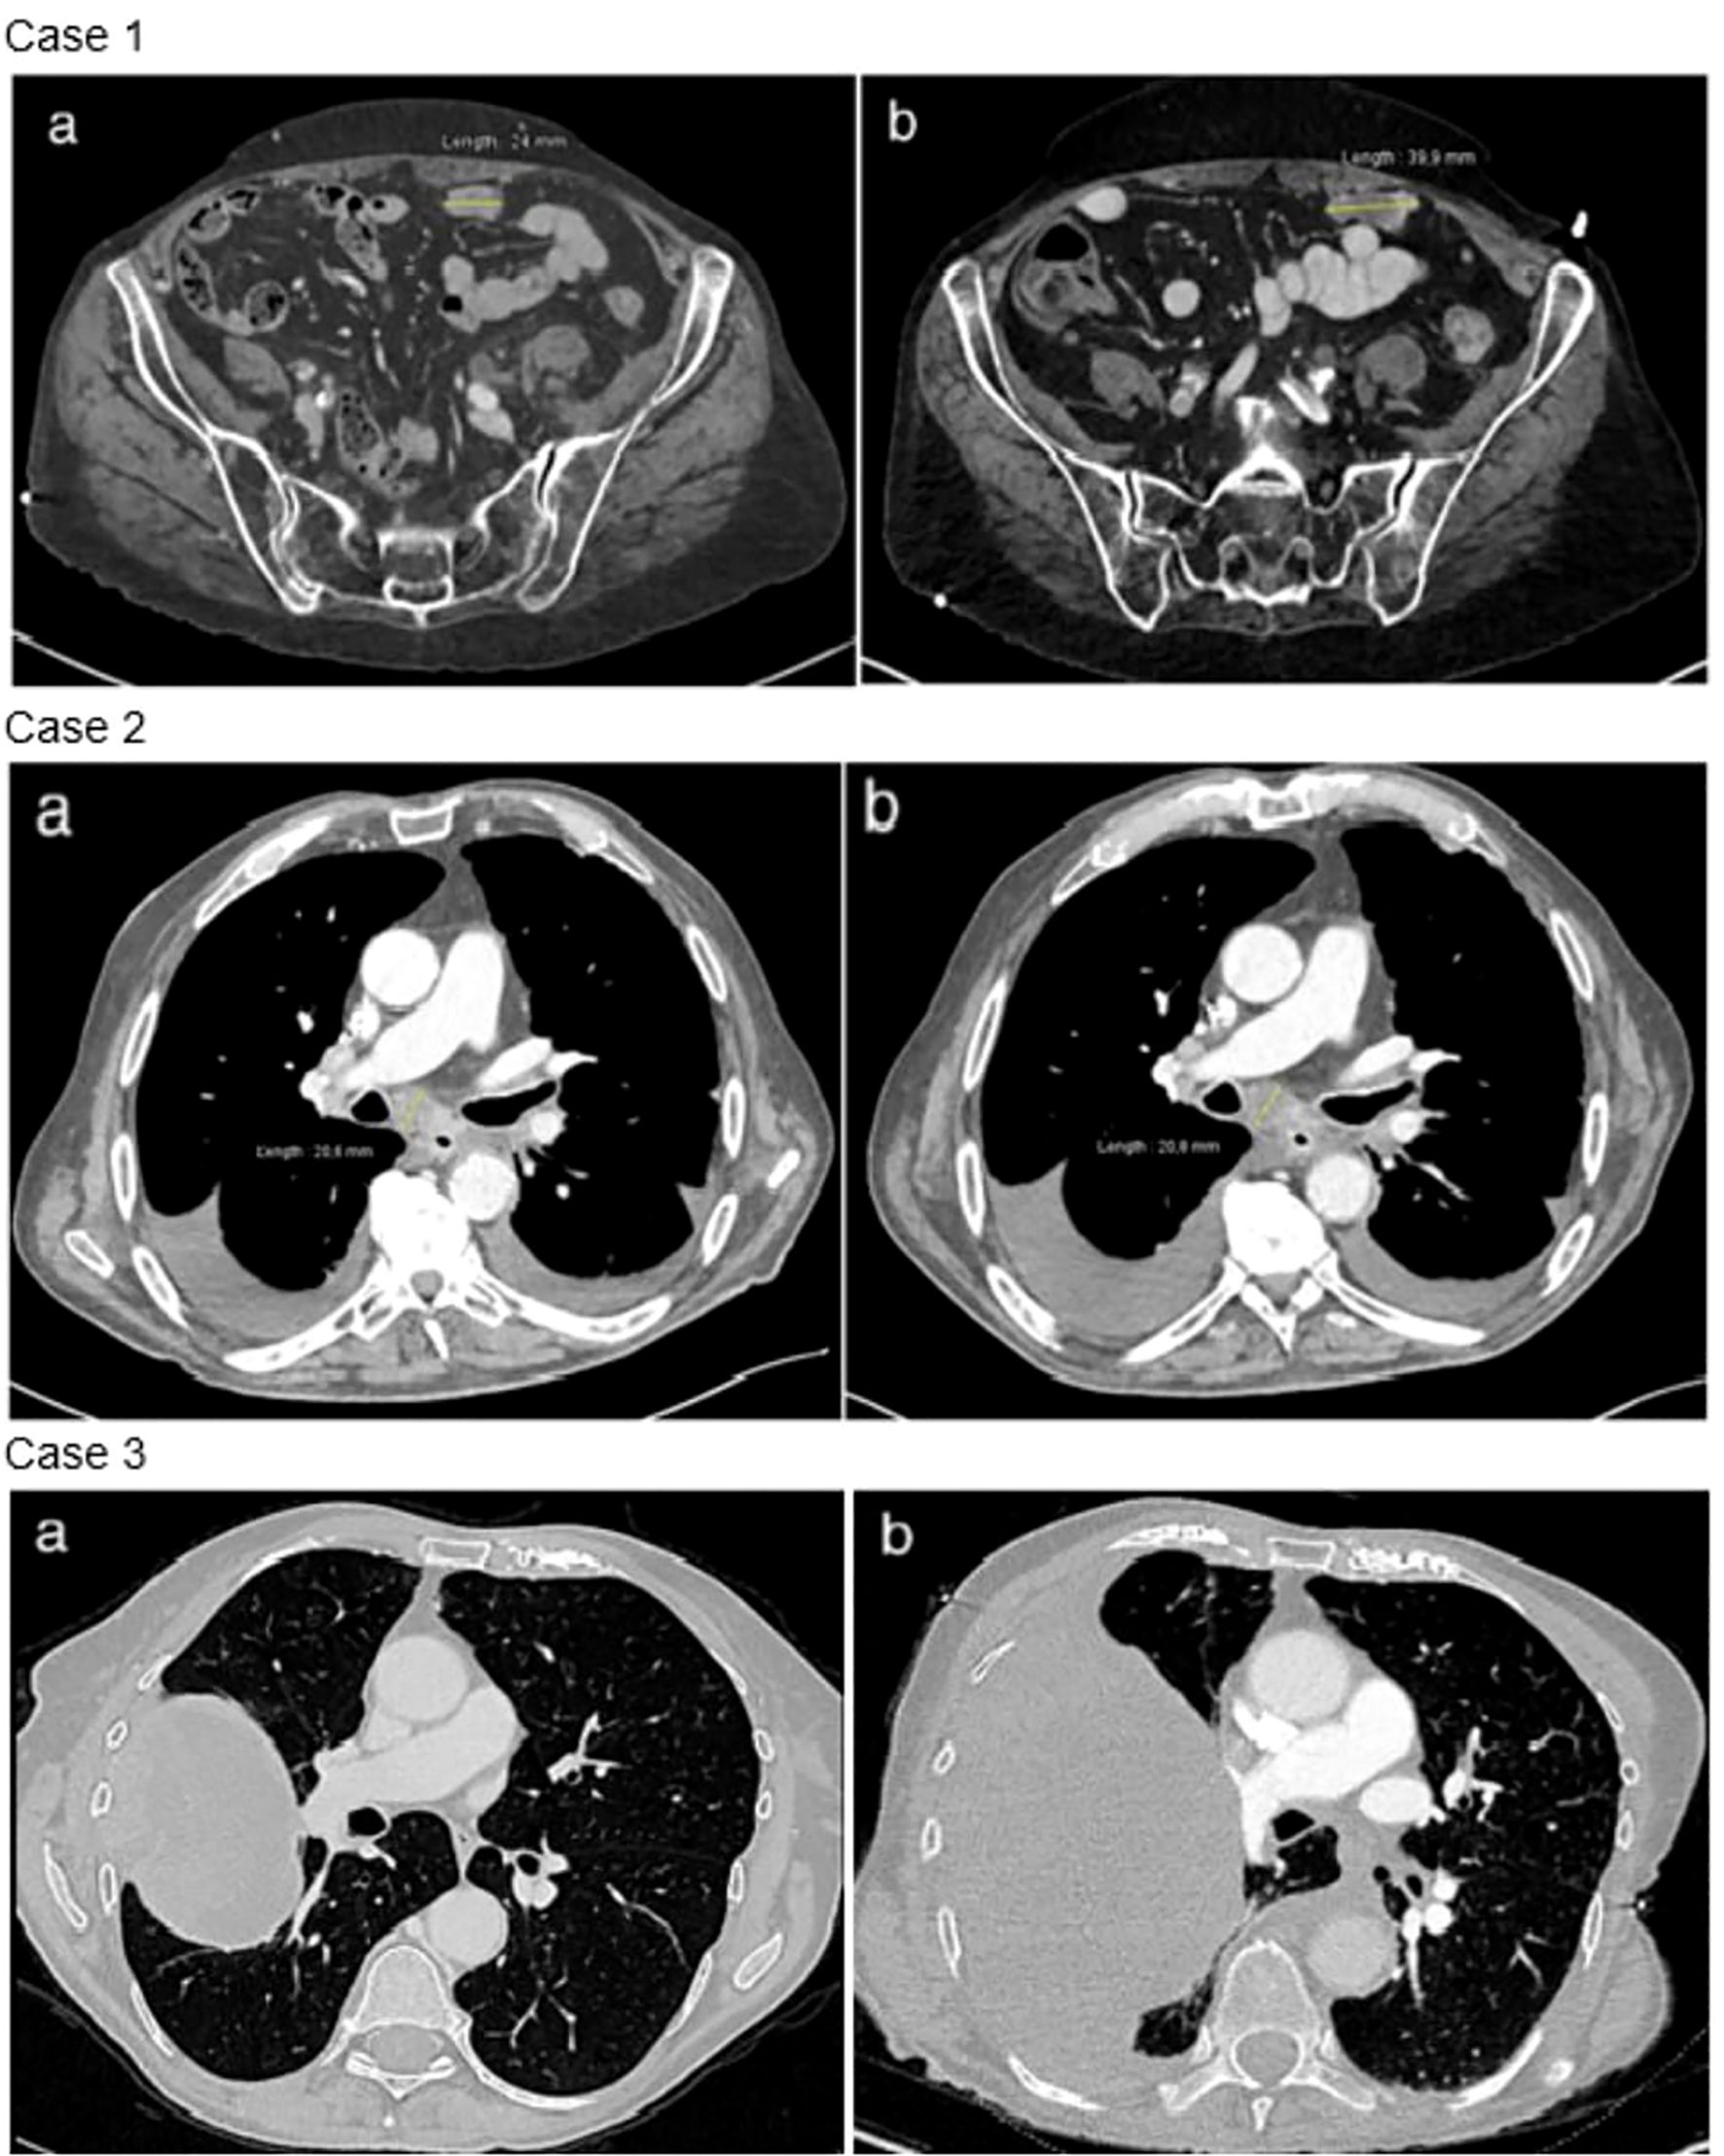

Two pathogenic NF1 mutations were identified (Table 1). Following TB proposition, the patient was started on trametinib in March 2023. At the onset of treatment, the patient had an ECOG of 2 and the Charlson score was 7 points. The treatment course was complicated by a grade 3 skin rash, requiring topical corticosteroid treatment and oral doxycycline. The first CT scan was performed at 7 weeks, showing progressive disease with a 70% increase in size of the lesions, per RECIST criteria (Figure 3). Treatment was discontinued, and the patient died rapidly.

CT scan images of three cases. Case 1 shows two scans of the pelvic region: (a) a scan indicating a measurement of twenty-four millimeters, and (b) a scan with a measurement of thirty-five point six millimeters. Case 2 presents chest scans: (a) and (b) with a measurement of twenty-nine point eight millimeters. Case 3 includes another set of chest scans: (a) with a visible large mass, and (b) showing surrounding lung areas.

Figure 3. Radiological evolution under trametinib. Case 1: disease progression between baseline thoraco-abdominal computed tomography (a) and after 7 weeks of trametinib (b). Example of a peritoneal metastasis. Case 2: stable disease between baseline thoraco-abdominal computed tomography (a) and after 6 weeks of trametinib (b). Case 3: disease progression between baseline thoraco-abdominal computed tomography (a) and after 8 weeks of trametinib (b).

After 6 weeks of trametinib, a CT scan showed stable disease per RECIST criteria (Figure 3). The clinical course was then complicated by an accidental fall and a hip fracture, followed by a heart failure with acute pulmonary edema. Trametinib treatment was immediately suspended, and the patient passed away 2 weeks later.

Second-line treatment with paclitaxel and bevacizumab was administered for 3 cycles until January 2022. Molecular analysis revealed a mutation in a splice donor consensus sequence of the NF1 gene with a gain of the mutated allele, based on the allele frequency and potentially resulting in partial NF1 inactivation (Table 1). No activating co-mutation of the RAS/MAPK pathway was identified, notably no RASA1 alteration. Subsequently, treatment with 2 mg of trametinib was initiated in February 2023. The patient had a ECOG 2 and a Charlson comorbidity index of 9 points. She experienced a grade 1 cutaneous rash and diarrhea. After 8 weeks of treatment, the CT scan showed thoracic and CNS progression (Figure 3). Trametinib was discontinued and, due to a rapid deterioration, the patient was started on best supportive care and died in April 2023.